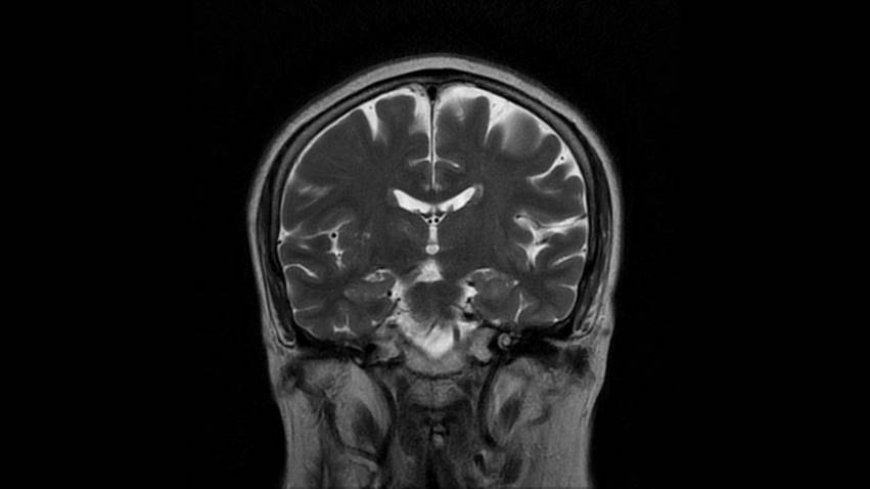

MRI of Brain

Coronal T2